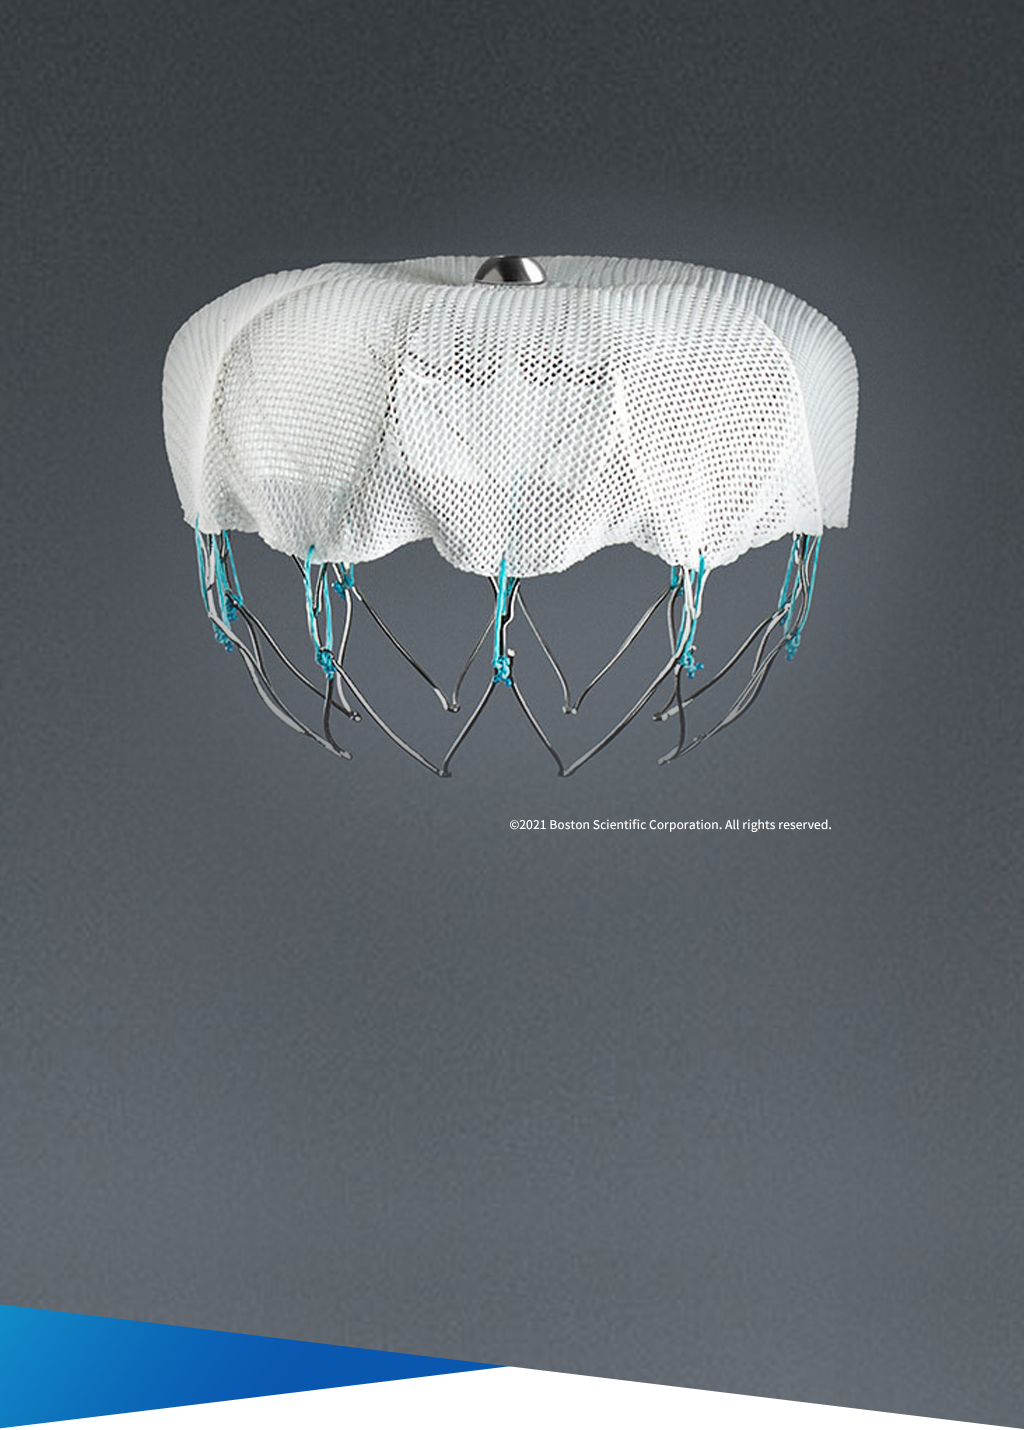

WATCHMANとは

評価されるWATCHMAN

WATCHMANはワルファリンやそのほかの抗凝固薬(エリキュース、イグザレルト、リクシアナ、プラザキサ)を長期間服用できない非弁膜症性心房細動患者さんに対する代替療法です。脳卒中リスクをそれらの抗凝固薬と同等に低減することに加えて、それらの投与を中止することで出血のリスクを低く抑えることができます。

WATCHMANのメリット

- 抗凝固薬を長期間服用できないNVAF(非弁膜症性心房細動)患者さんに対して、ワルファリンと同等の脳卒中リスク低減効果が期待できます。

- 抗凝固薬による長期出血リスクを低減することが期待できます。

- 1回限りの手技で完了します。

非弁膜症性心房細動の患者さんでは、脳卒中の原因となる血栓の90%以上が左心房に起始する左心耳(LAA:Left Atrial Appendage)で形成されたものです。

WATCHMANはこのLAAを閉鎖して血栓の形成を防ぎます。手技は経静脈的心房中隔穿刺法であり、カテーテル室において全身麻酔下で実施します。

WATCHMANを展開し、LAAに留置します。

WATCHMANを覆うように内皮化が進み、LAAが永久的に閉鎖されます。患者さんは、手技後約45日間は抗凝固薬の内服を継続します。経食道心エコーで閉鎖していることを確認します。

WATCHMANの働き

左房に存在する左心耳(LAA)というポケットに血栓が形成され、これが脳やほかの臓器に流れて梗塞(塞栓)を引き起こします。

WATCHMANは心臓の左心耳(LAA)と呼ばれる部分に留置されます。

WATCHMANは時間が経つと、内皮に覆われて完全にLAAを閉鎖します。

WATCHMANは心臓内に永久留置をするデバイスで、脳卒中の原因となる血栓を形成することが多い、左心耳(LAA:Left Atrial Appendage)を直接閉鎖します。血栓形成の好発部位が消失することで、予防として内服していた抗凝固剤を中止できます。